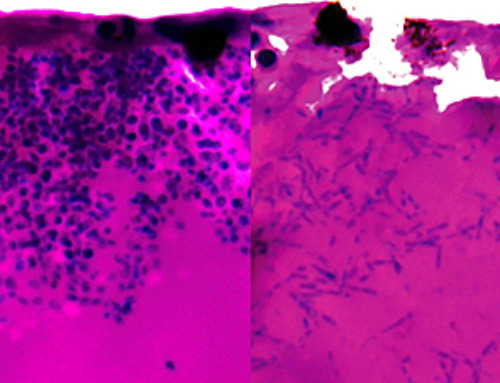

Scientists Discover Cheap Material That Kills Deadly Superbugs

A new sulfur-rich antimicrobial polymer shows strong effectiveness against fungal and bacterial pathogens and may offer an affordable solution to antimicrobial resistance. Antimicrobial resistance is creating growing challenges for both healthcare and food production, [...]